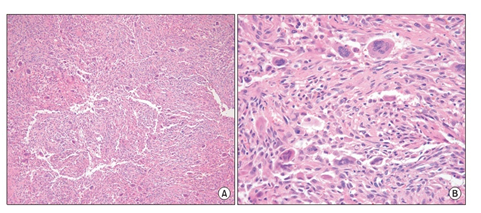

Grossly, pigmented villonodular synovitis appears as a proliferative synovial process with brownish villo-nodular fronds in the affected joints (Figure 3).2 Multiple yellow to brown nodules could be detected in localized types and in the pes anserine bursa (Figure 4). Histopathologically, the tumor is generally represented by many mononuclear histiocytic cells and irregularly interspersed multinucleated giant cells. Hemosiderin pigments could also be detected. Some foamy histiocytic cells may individually interspersed or form clusters (Figure 5).8 Osseous, cartilaginous, and soft tissue involvement was also seen .Fine needle aspiration cytology reveal a few clustered and scattered plump spindle cells containing hemosiderin-pigments and several scattered multinucleated giant cells (Figure 6).

Figure 5 Villo-nodular mass showing many mononuclear histiocytic cells and irregularly interspersed multinucleated giant cells. Hemosiderin deposits are found (H&E staining A×100, B×400).